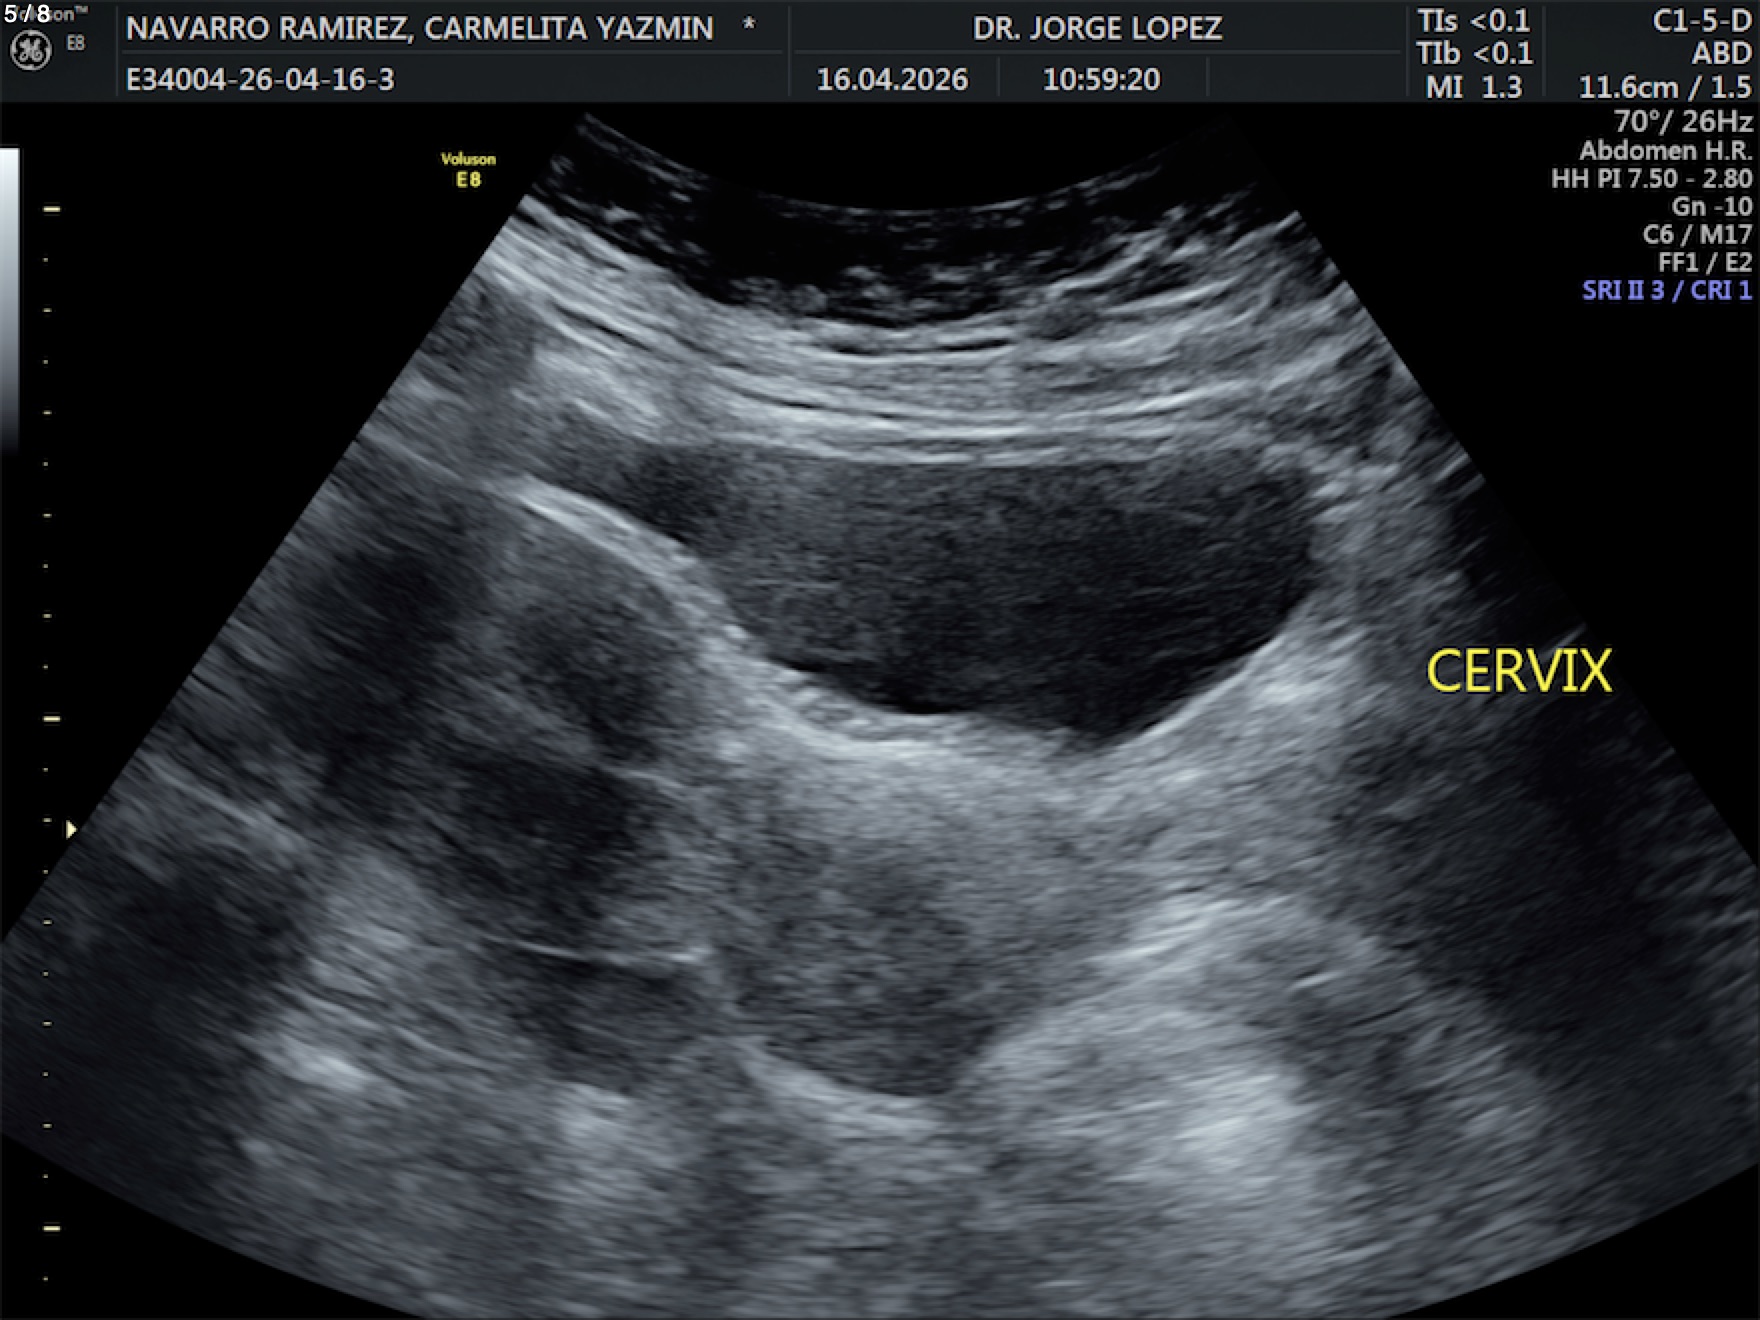

Navarro Ramirez Carmelita Yazmin - Unnamed